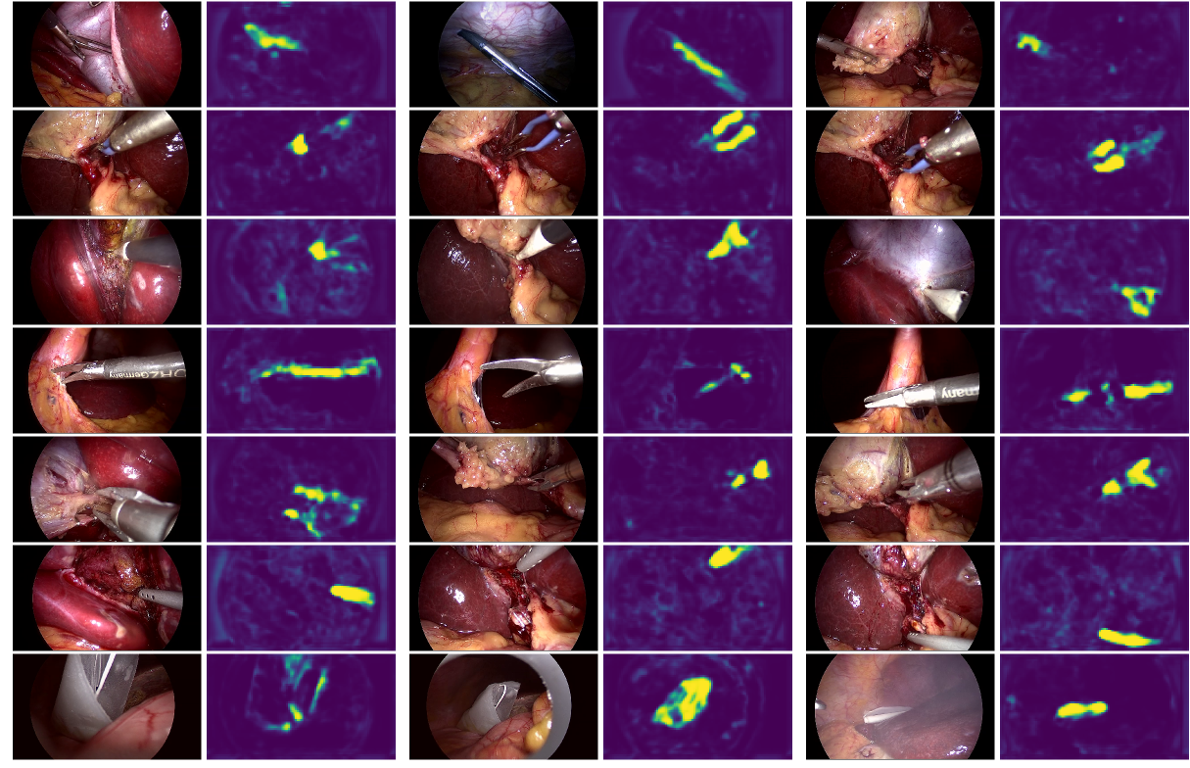

In Figure 4, we present additional results for the architecture FCN_ESP_MM_Msk. In the figure, we see which features the network finds most discriminative about each of the tools. Ideally, we aim to localize the working end of the tools only, as the shaft does not usually contain tool-specific features. In Figure 4, we can see that for scissors and irrigator (row 4 and 6 respectively) the shafts themselves are very distinctive and discriminative. In the case of scissors, the brightest detection corresponds to the shaft. This may explain why the localization AP values for scissors are the lowest among all tools, as the annotated bounding boxes are defined over tool tips only (see column 1 in Figure 3). Specimen bag (last row) is an exception since it is not connected to a shaft. We should also note that the second tool, bipolar, is not fully detected. The network detects the blue insulated section of the forceps but not the metal tips. Our intuition is that they look very similar to those of grasper and hence cannot be used to discriminate one tool from the other. Additional qualitative results can be seen in the supplementary video (https://youtu.be/7VWVY04Z0MA).

Refer to caption

Figure 4: Input images (left) and corresponding localization maps after sigmoid layer (right). Each row shows 3 examples of the same tool. The tools in rows 1-7 are presented in the following order: grasper, bipolar, hook, scissors, clipper, irrigator, specimen bag. These results correspond to architecture FCN_ESP_MM_Msk. (Best seen in color)